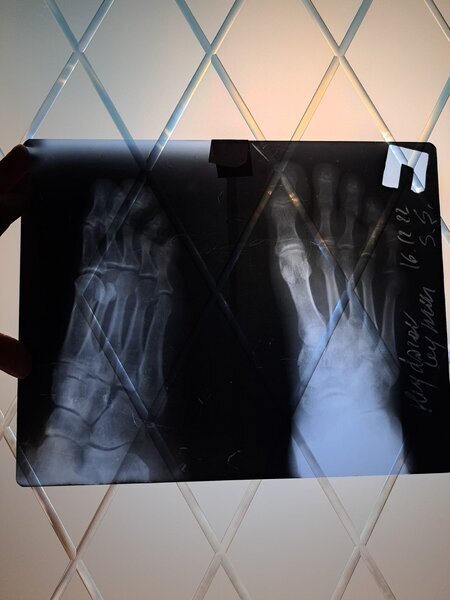

"Şikayətim Elmi-Tədqiqat Travmatologiya və Ortopediya İnstitutunda qeyri-rəsmi çalışan rezident Ağa Mirməhəmməd Mirhaşım oğlundandır. Həyat yoldaşım Ceyhun Heydərov avtomobil qəzası keçirdiyi gün Travmatologiya İnstitutuna müraciət etmişdir. İlkin baxış və rentgen müayinələrindən sonra özünü həkim kimi təqdim edən Ağa Mirməhəmməd rentgen nəticələrini düzgün oxuya bilməmiş və yoldaşımı arxayın edərək heç bir sınıq olmadığını, əzilmə və sıyrıq olduğunu demiş, xəstəni evə yola salmışdır.

Bir neçə gün sonra ayağın göyərdiyini və şişdiyini gördüyümüz üçün yenidən Travmatologiya İnstitutuna müraciət etmişik. Bu dəfə bir digər həkim travmatoloq 16.12.2022-ci ildə çəkilmiş elə həmin rentgen nəticələrinə baxaraq ayağın topuq nahiyəsində sınıq olduğunu aşkar etmiş. Təkrar KT müayinəsi etdirmiş və sınıq olduğunu tam dəqiqliklə təsdiqləmişdir. (Eyni zamanda tam əmin olmaq üçün özəl klinikalardan birinə də müraciət etmişik)

Sınıq ilk gün Ağa Mirməhəmməd tərəfindən aşkarlanmadığı və dəqiq diaqnoz qoyulmadığı üçün sınıq yerdəyişmiş və nəticədə yoldaşım Ceyhun Heydərov 30.12.2022-ci ildə əməliyyat keçirmişdir".